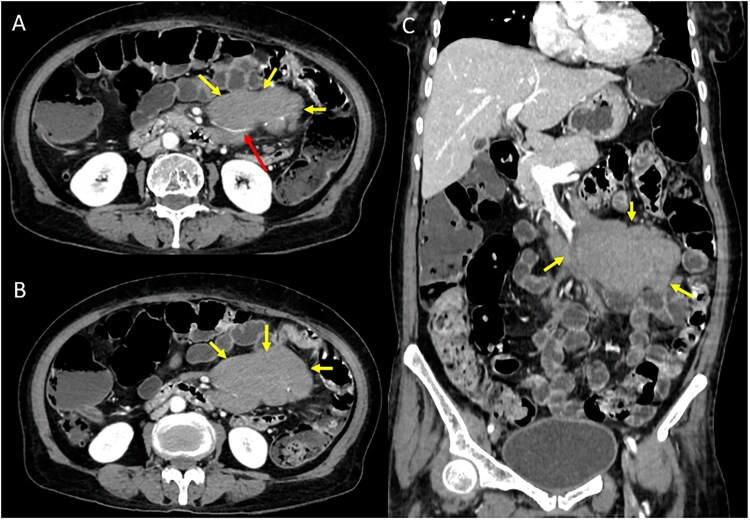

67岁女性2型糖尿病患者表现为顽固性疼痛口腔糜烂和胸部紫色病变,口服皮质类固醇反应最小。由于既往食欲下降、体重减轻且治疗效果不佳,进一步评估发现c反应肽、desmoglin -3抗体、碳水化合物抗原19-9升高,腹膜内分叶状均匀增强的淋巴结肿块,后者提示淋巴瘤。口腔黏膜组织病理学提示副肿瘤性天疱疮。患者转至肿瘤科接受进一步治疗。该病例强调了对具有非典型组织病理学的顽固性皮肤粘膜病变的老年患者进行彻底评估的重要性。

A 67-year-old female with type-2 diabetes mellitus presented with recalcitrant painful oral erosions and violaceous chest lesions, that responded minimally to oral corticosteroids. Due to history of decreased appetite, weight loss and poor therapeutic response, further evaluation was performed, revealing elevated C-Reactive Peptide, Desmoglein-3 antibody, Carbohydrate Antigen 19-9, and intraperitoneal lobulated homogeneously enhancing nodal mass, the latter indicating lymphoma. Histopathology from oral mucosa was suggestive of paraneoplastic pemphigus. The patient was referred to oncology department for further management. This case underscores the importance of thorough evaluation in elderly patients with recalcitrant mucocutaneous lesions with atypical histopathology.